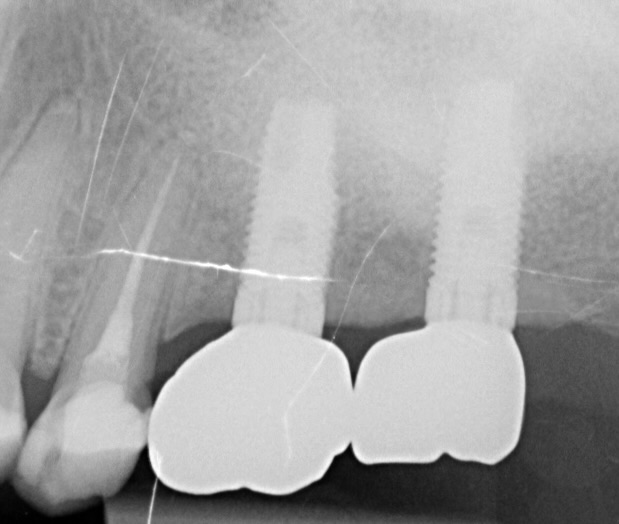

Figure 17.

Periapical x-ray 2 years after loading.